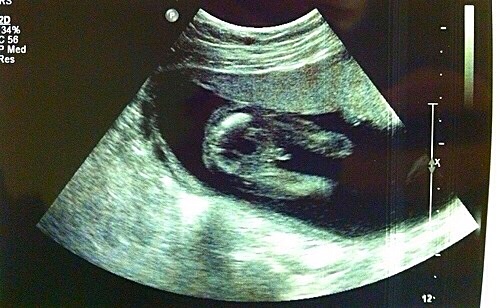

This is the penis and scrotum Attachment 13551

All boy !

Boy